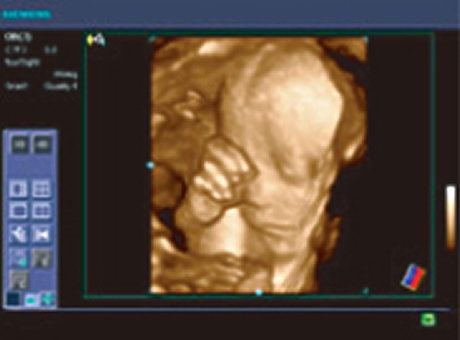

| 超音波検査 | 当院では検診の際、必ず超音波検査を行っております。 当院は最新鋭の4D超音波診断装置【ACUSON X700】を導入しています。 通常は2D超音波検査ですが、ご希望により4D超音波も行っています。 ※超音波の映像をDVDに録画します。赤ちゃんの成長記録の記念にしてください。 (DVDは当院で用意しております。録画は無料です。) ※超音波の映像を一緒に見られるモニターがありますので、ご主人やお子様とぜひ一緒にご来院ください。 |

| 4D超音波とは… | 4D超音波は赤ちゃんの様子をリアルタイムで観察できます。 ■4D超音波 - 立体画像を動画として見ることが出来ます ■3D超音波 - 立体静止画像です ■2D超音波 - 通常の検診時に見ている平面画像です |

赤ちゃんの様子をリアルタイムで観察し、DVDに録画いたします。 対象は妊娠20週~30週の方(24週~28週が最適)です。 ![]() ![]() ![]() 赤ちゃんの顔の向きや羊水の量などにより、うまく見えない場合もあります。 その場合には日を改めて無料でお撮り直しいたします。 |